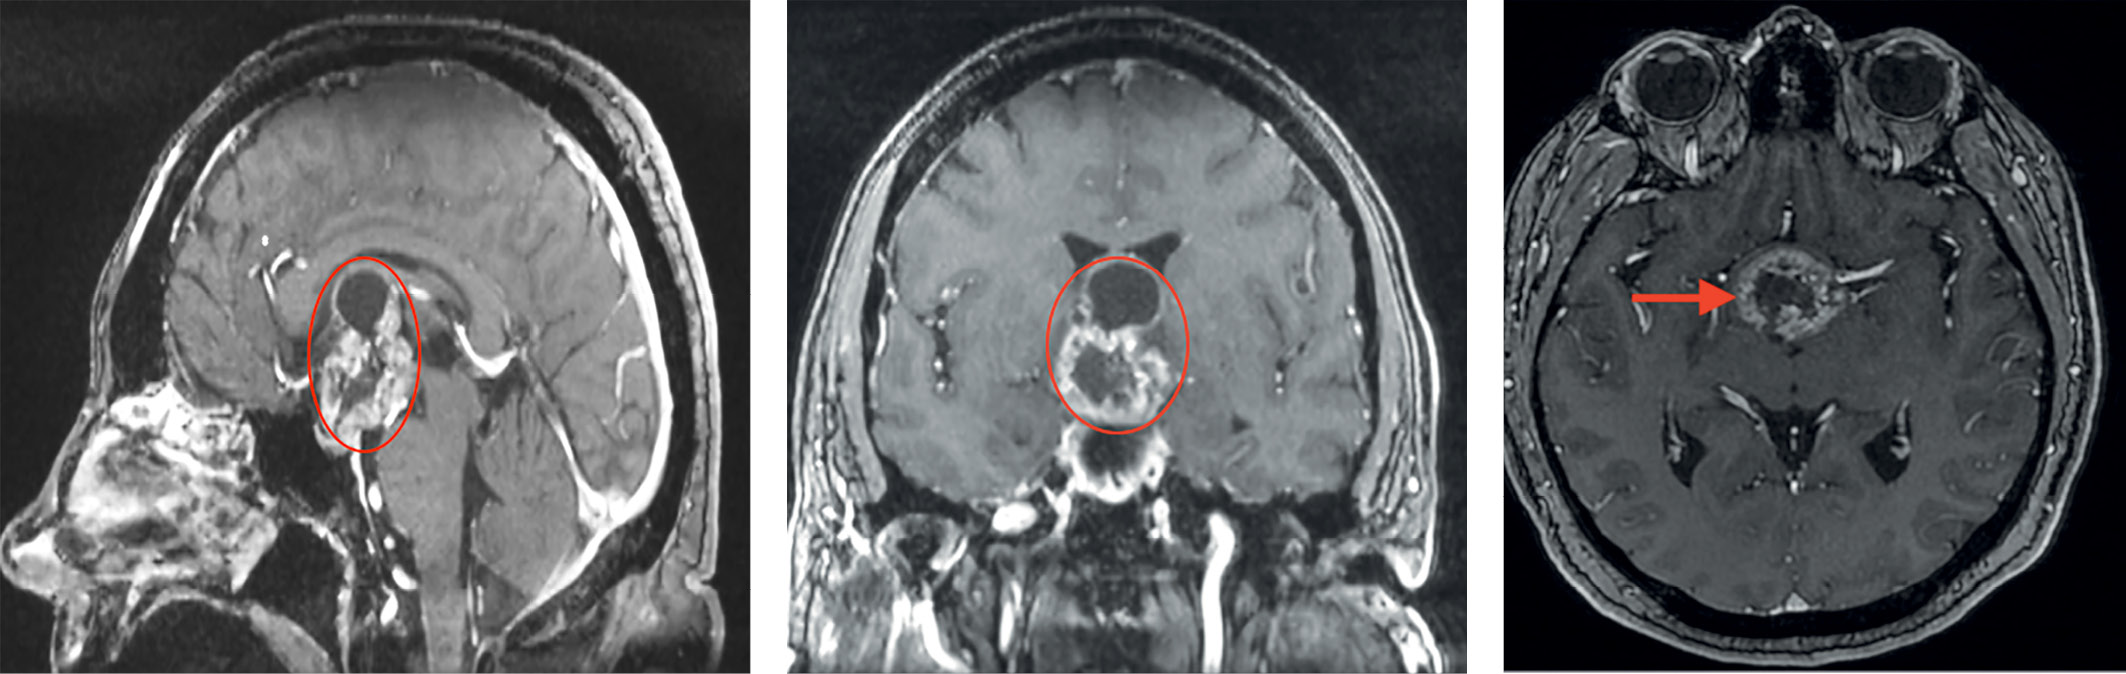

По данным МРТ-исследования признаков интракраниальных осложнений не выявлено, фрагменты капсулы опухоли в области III желудочка (рис. 3).

Рисунок 3. МРТ пациентки З. после операции. На фоне послеоперационных изменений визуализируются фрагменты капсулы опухоли в области III желудочка (указаны стрелкой).

Figure 3. MRI of patient Z. after surgery. Against the background of postoperative changes, fragments of the tumor capsule are visualized in the region of the third ventricle (indicated by an arrow).